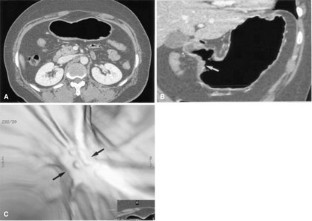

Figure 1